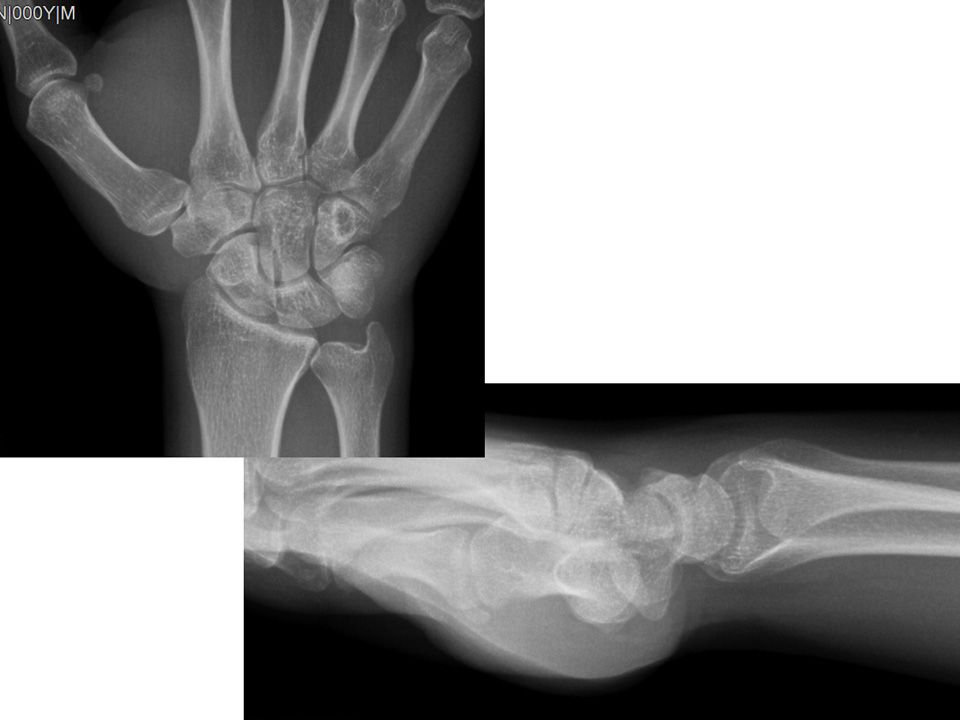

25 yaş, erkek, , sağ el dominant2.5 yıl önce burkulma sonrası sağ el bilek dorsal orta hatta mevcut ağrıFTR, istirahat ateli ve NSAID’e rağmen geçmemişWatson shift testi +, parmak ekstansiyon testi +